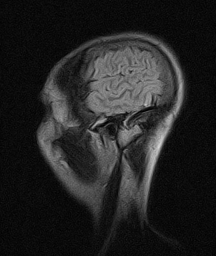

Det er vist kendt at mennesker med sklerose føler sig mere trætte i almindelighed. Hvorfor er jeg ikke helt klar over men tænker at min hjerne arbejde på højtryk for at kompenserer for nogle defekter og bruge mere energi på at behandle tanker og indtryk.

Og det er her hvilen og roen kommer ind. Hjernen er nødt til at få mere hvile og ro for at kunne fungerer. Hvis jeg sover dårligt eller ikke får min hvile træder min kognitive problemer mere tydeligt frem.